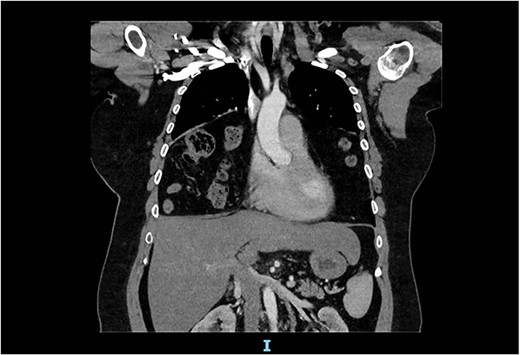

The spirometry results from her General Practitioner showed a restrictive pattern with FVC of 2.08L (55% predicted), FEV1 of 1.62L (54% predicted) and FEV1/FVC ratio of 0.78 (96% predicted). Her chest X-ray demonstrated a large hiatus or congenital hernia (Fig. 1). Subsequent computed tomography (CT) of the chest, abdomen and pelvis showed a large 88 × 48-mm defect of the anterior diaphragm consistent with MH. Hernial contents extended to the superior mediastinum and were primarily large bowel and omentum, with no intestinal obstruction (Figs 2–4).

Arterial contrast CT of the chest. Coronal slice transecting the midpoint of the chest cavity showing herniation of large bowel, small bowel and omentum into the chest cavity.